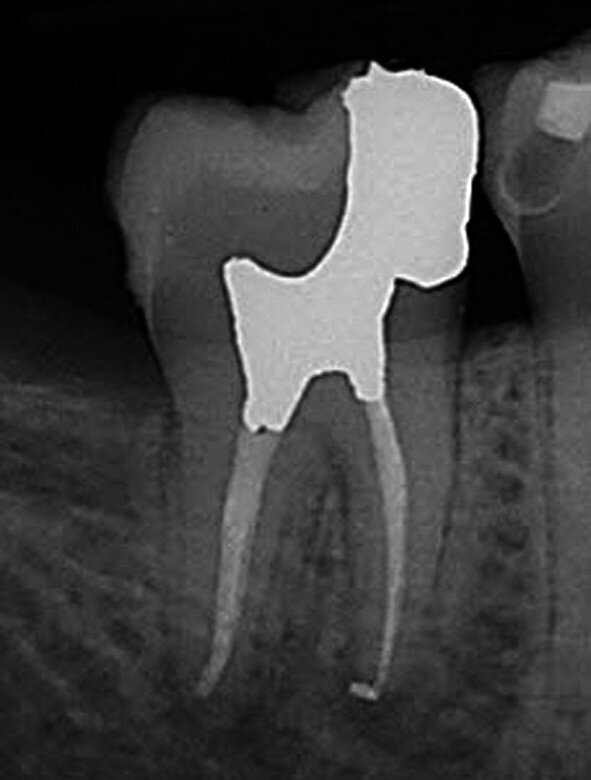

Figs. 4a et b : Cavités d’accès réalisées dans une molaire préparée pour une couronne et requérant un traitement canalaire (à gauche). Radiographie postopératoire (à droite) montrant le résultat admirable de la mise en forme du canal radiculaire, du nettoyage et de l’obturation – malgré la dimension minimale de l’orifice d’accès. À noter le plafond de la cavité pulpaire qui subsiste largement. (Photos : fournies par le Dr Steve Baerg)